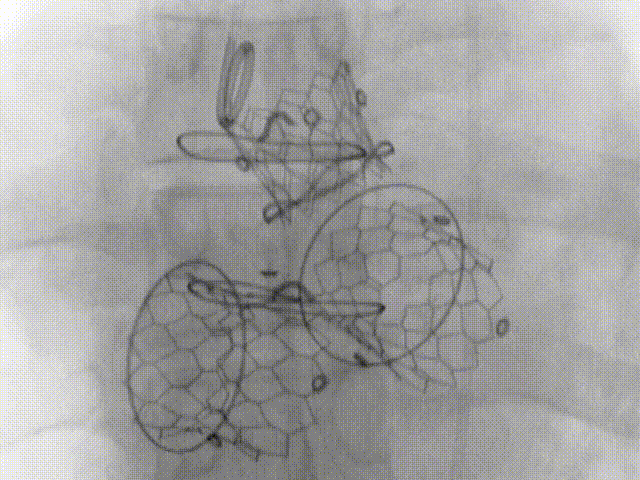

沪豫联合手术团队于3月5日为患者实施了主动脉瓣、二尖瓣、三尖瓣联合“瓣中瓣”置换手术。由于患者病变复杂,团队采用了三种不同路径植入三个瓣位(经股动脉主动脉瓣位23# 瓣中瓣植入,经心尖二尖瓣位27#瓣中瓣植入,经股静脉三尖瓣29#瓣中瓣植入),3枚瓣中瓣植入位置完美,功能理想。术中血流动力学平稳,无传导阻滞和流出道梗阻等并发症发生,几乎无出血。手术取得了圆满成功。

术后造影显示“瓣中瓣”位置完美、功能理想